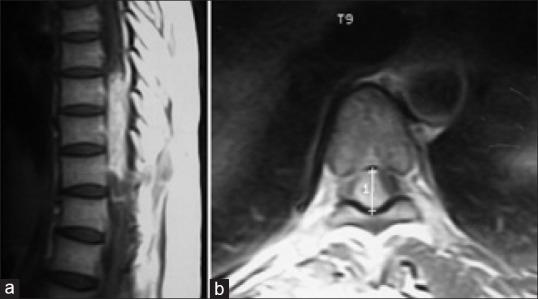

Spinal schwannomas account for about 25% of primary intradural spinal cord tumors in adult. The prognosis for spinal schwannomas is excellent in most cases. Complete resection is curative. However following subtotal removal, recurrence develops after several years. We describe a case of recurrent spinal schwannoma who had been operated twice before for same disease. The possible cause of recurrence and difficulties in reoperation are discussed.

脊髓神经鞘瘤约占成人原发性硬脊膜内脊髓肿瘤的25%。在大多数情况下,脊髓神经鞘瘤的预后良好。完整切除可治愈。然而,次全切除后,数年后会复发。我们描述了一例复发性脊髓神经鞘瘤病例,该患者曾因同一疾病接受过两次手术。讨论了复发的可能原因及再次手术的困难。